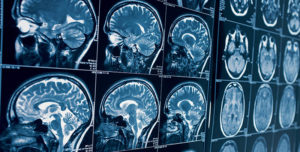

Магнитно-резонансная томография — это метод диагностической визуализации, который не использует излучение и позволяет отображать изображения органов вашего тела с высоким разрешением. Нужно отметить, что пройти МРТ можно тут https://istra-paracels.ru/diagnostika/mrt, поэтому перейдите на сайт и узнайте все подробности.

Магнитно-резонансная томография считается одним из величайших достижений века в области медицинской диагностической визуализации. С помощью изображений, полученных при обследовании, можно провести анализ неврологических, ортопедических, абдоминальных, шейных и сердечных заболеваний.

Эта процедура также показана для диагностики опухолей, дегенеративных заболеваний, тромбов и травм. Магнитно-резонансная томография очень эффективна для диагностики рассеянного склероза, опухолей головного мозга и гипофиза, инфекций головного мозга и суставов, инфекций спинного мозга, травм плеча, тендинита, раннего выпота, разрыва связок в запястье, колене и голеностопе.